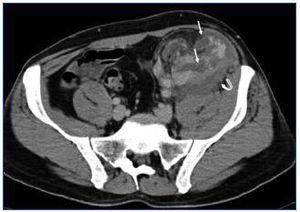

Se realizó una ecografía-Doppler de urgencia que informaba injerto en fosa ilíaca izquierda (FII) de 121 mm con aumento de la ecogenicidad cortical, buena perfusión, IR: 1, identificándose una colección organizada perirrenal de 93 x 37 x 60 mm que se interpretó como un hematoma. Para completar el estudio se realizó una tomografía computarizada con contraste que mostró realce de todo el riñón con dos imágenes lineales hipoecoicas, que se interpretaron como fractura del polo inferior del injerto (figura 1 y figura 2). No se observaron imágenes de aneurisma ni de tumor renal. Ante la estabilidad hemodinámica y el diagnóstico de ruptura renal evolucionada se descartó tratamiento quirúrgico urgente. Se realizó una primera sesión de hemodiálisis; coincidiendo con ésta presentó reanudación de la diuresis en 48 h con progresiva mejoría de los parámetros analíticos. Se descartó el diagnóstico de RA dada la evolución favorable del paciente sin haber tomado otras medidas terapéuticas y que tenía los niveles de inmunosupresores en rango.

Figura 2. Tomografía computarizada del injerto que muestra dos imágenes lineales hipoecoicas compatibles con fractura del polo inferior (flechas finas).